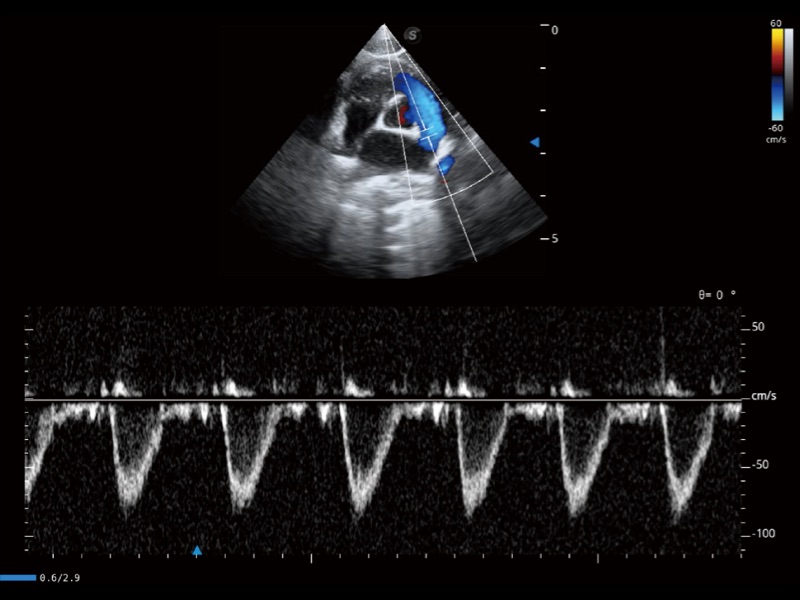

通过创新的 Matrix E自适应滤波器和超长时间域算法,极大提升超低速微细血流的检出能力,同时更精准地滤除软组织和噪声信号,为兽用医生提供以往无法通过常规血流获得的疾病诊断信息。

通过360度任意调节3条M型取样线,在同一心动周期上观察心脏不同位置的运动曲线,得到准确的心功能测量数据,有效评估心肌运动及左心室功能。